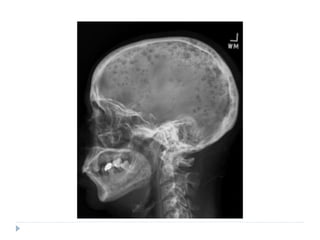

RADIOGRAPHIC FEATURES

 Multiple well-defined punched out radiolucencies

 Especially evident on the skull radiograph

 Jaws are involved in 30%